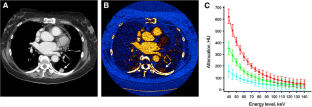

Fig. 3